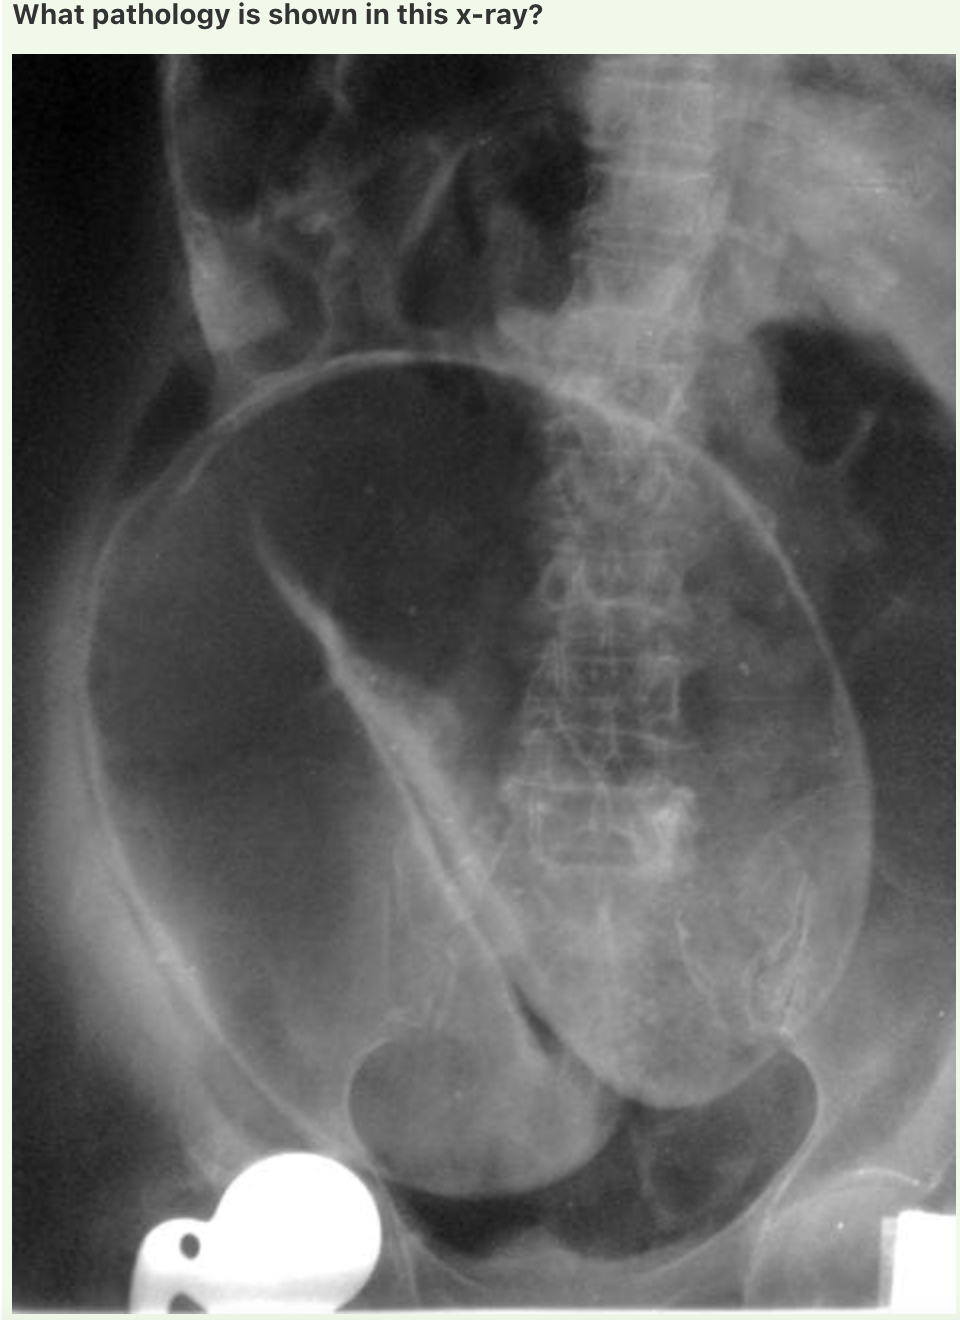

Volvulus

Classic coffee bean sign (omega sign) of a sigmoid volvulus.